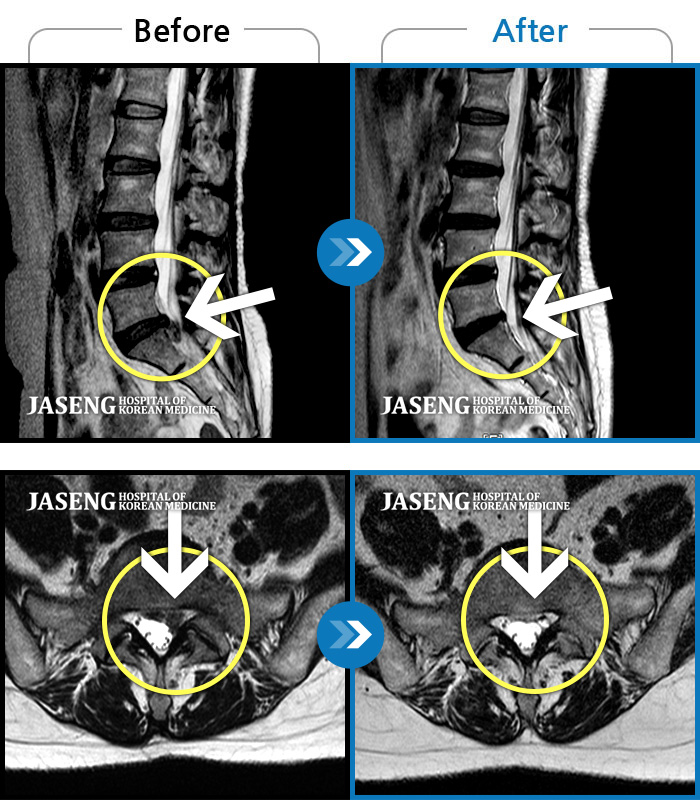

• 허리디스크